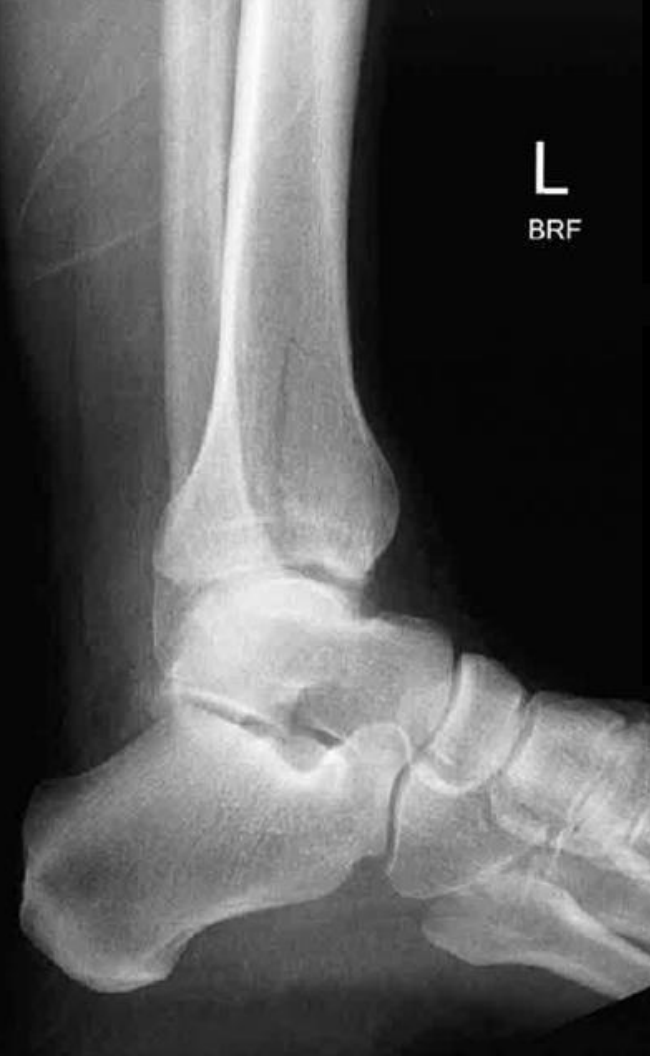

6

abnormality

A

minimally displaced fracture distal tibia with intra articular involvement